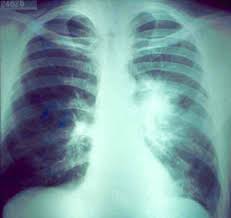

NEUMOTORAX

El neumotórax se define como la presencia de aire dentro de la cavidad pleural que provoca el

colapso pulmonar del tejido adyacente.

Los podemos clasificar en función de la causa que los ha producido y en función de la

enfermedad pulmonar de base. Pueden ser espontáneos, traumáticos o yatrogénicos en

función de la causa y a su vez los espontáneos los podemos dividir en primarios o secundarios

en función de la patología respiratoria

El  neumotórax traumático se divide en cerrado o  abierto en función de la

presencia o no de herida penetrante, con mucha frecuencia se acompaña de hemotórax de

cuantía variable. El barotrauma suele darse  en pacientes sometidos a ventilación mecánica,

relacionándose este hecho con el uso de volúmenes corrientes y PEEP elevados.